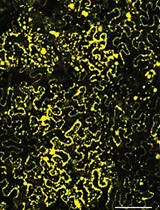

Ex-vivo Skin Permeability Tests of Nanoparticles for Microscopy Imaging

Delivery of drugs through the skin is a major challenge in the field of drug delivery systems. Quantification of materials, and specifically nanoparticles, within the skin layers is essential for the development of advanced topical and transdermal delivery systems. We have developed a technique for ex-vivo segmentation and evaluation of human skin samples treated with fluorescent nanoparticles. The method is based on horizontal cryosections of skin samples, followed by confocal microscopy and image analysis. This protocol is relatively simple to perform with basic histological tools, thus it can serve for various dermatology assays.